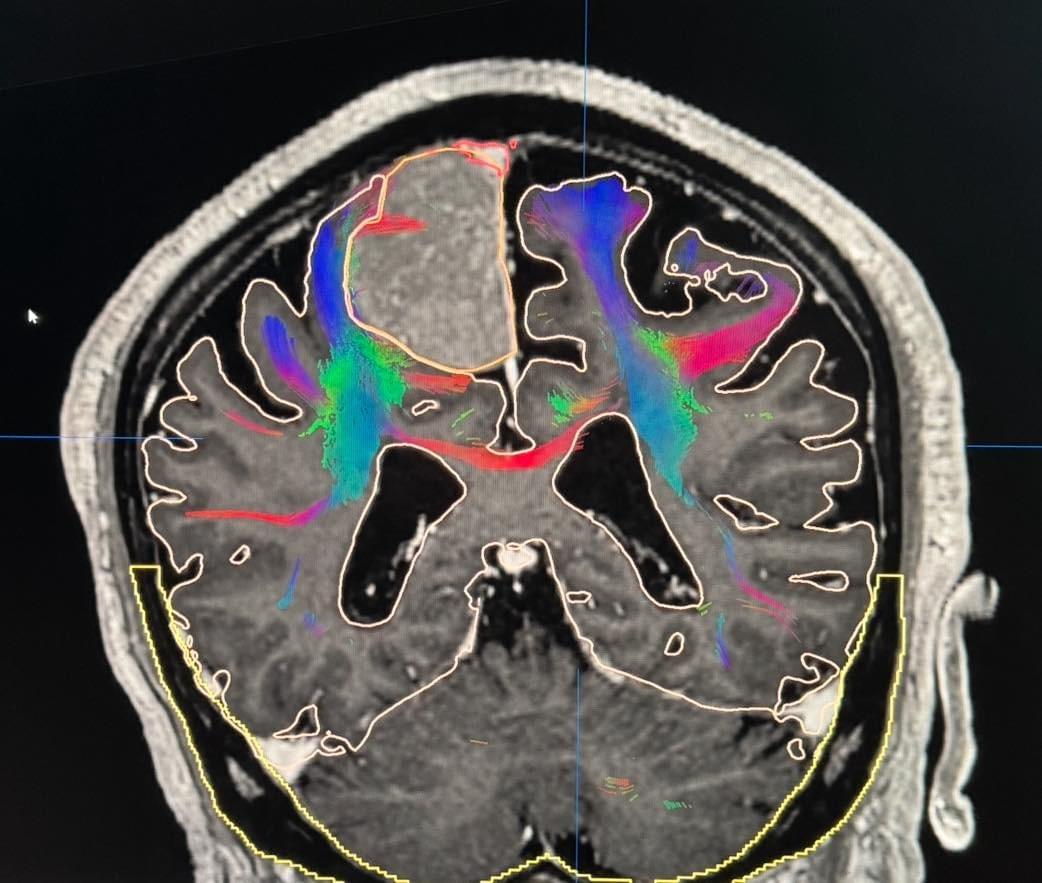

80歲的老年男性,合併一些內科共病,因為漸進性的右側肢體無力(尤其是右腳)來到醫院。詳細檢查後發現一顆左側運動區中央大靜脈竇旁的腦膜瘤。腦膜瘤還不小,重點是有中央大靜脈竇的侵犯與鄰近運動腦皮質的白質水腫。

手術很平順的完成,我非常小心的保留所有鄰近的靜脈以及盡可能不拉扯鄰近的運動皮質。腫瘤幾乎99%以上都完成切除,只有些微侵犯中央大靜脈竇的部分被我保留下來。

但手術後病患清醒沒多久就開始癲癇發作。雖然有預防性投藥,但癲癇很快發展到癲癇積重症。於是只好在加護病房上全鎮定並上多重抗癲癇藥物。鎮定藥物把病患腦波打平,再慢慢的逐一移除藥物。術後的磁振顯示99%以上的腫瘤切除,沒有出血沒有梗塞,但是有約8釐米的鄰近運動白質水腫。因此病患逐漸脫離癲癇與藥物的影響,術後兩週清醒之後右側肢體就幾乎癱瘓了(肌力一分)。